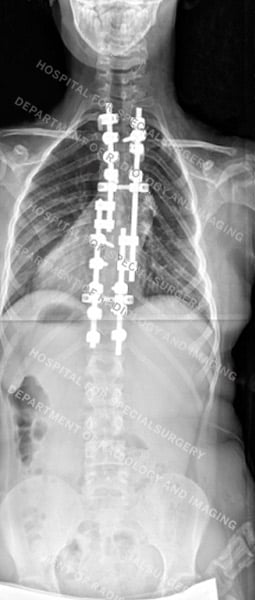

Posteroanterior (back-to-front) X-rays of dystrophic scoliosis (first image) and nondystrophic scoliosis (second image) after surgery

- Spinal fusion for scoliosis and, if present, kyphosis. This surgery involves realigning the spine and using metal rods and screws with bone grafts to achieve fusion.

Surgery to correct a dystrophic scoliosis curve can present special challenges, including the need to correct a kyphotic (rounding of the back) curve at the same time. These surgeries also carry a risk of pseudoarthrosis or non-union. To help minimize this risk, orthopedic surgeons at HSS use autograft from the patient’s iliac crest bone (part of the pelvis) to achieve the fusion, as opposed to the allograft often used in other scoliosis surgeries. These complicating factors often necessitate more than one surgery.